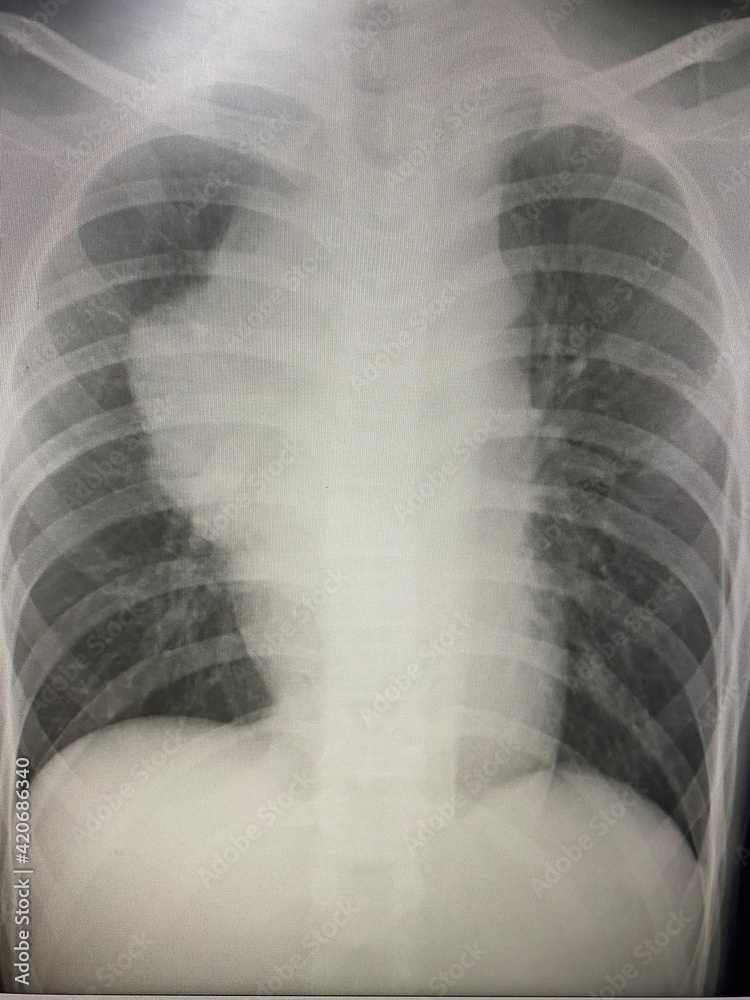

Chest Xray showed a right hilar shadow with speck of cal cifications

Chest Xray showed a right hilar shadow with speck of cal cifications Will A Chest X-Ray Show Mold Exposure Yet the effects of mold. — frequent symptoms of mold exposure. Mold exposure can be difficult to diagnose, as symptoms can be mistaken for other conditions and not everyone experiences the same symptoms. Mold grows in dark, damp places, like. — mold is a type of fungus. — mold exposure diagnosis. — indoor mold exposure is. Will A Chest X-Ray Show Mold Exposure.